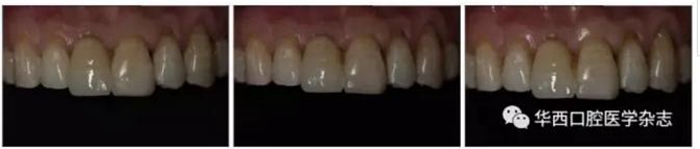

所有患者在單端全瓷樹脂粘接橋修復完成后進行定期隨訪。前述典型病例6個月、1年、2年的修復效果見圖5。修復6個月后,20顆單端全瓷樹脂粘接橋的6項評價指標均達到A級;修復完成后1年,1例修復體周圍齲達到B級,其余均正常;修復完成后2年,1例修復體周圍齲達到B級,1例修復體折斷達到B級,其余均正常(表2)。

左:6個月;中:1年;右:2年。

圖5 修復完成后隨訪不同時間的口內(nèi)像